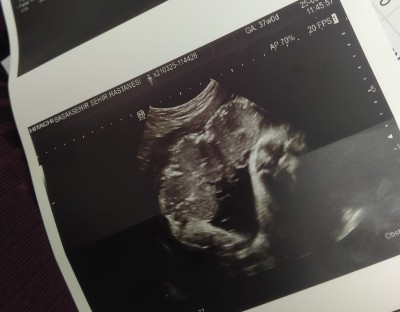

Ayaklar midemde ama sanki bebeğin yüz tarafı karnımın içine bakıyor değişik bir duruş popo göbeğimd gibi

Gebelik haftası 36+2

Ters durmuş burda ama doğum pozisyonuna geçmek üzere

Doktora da sormayı unuttum. Popo dışa dönük ya içe mi dönecek :)

Genelde öyle oluyor içe dönük oluyor

Yaaaa maaşallah subhanallah...sanki ayağa kalkmış gibi çok sevimli ya :) biz daha 11 haftalik olup minik olunca böyle pozlarımiz yok :)